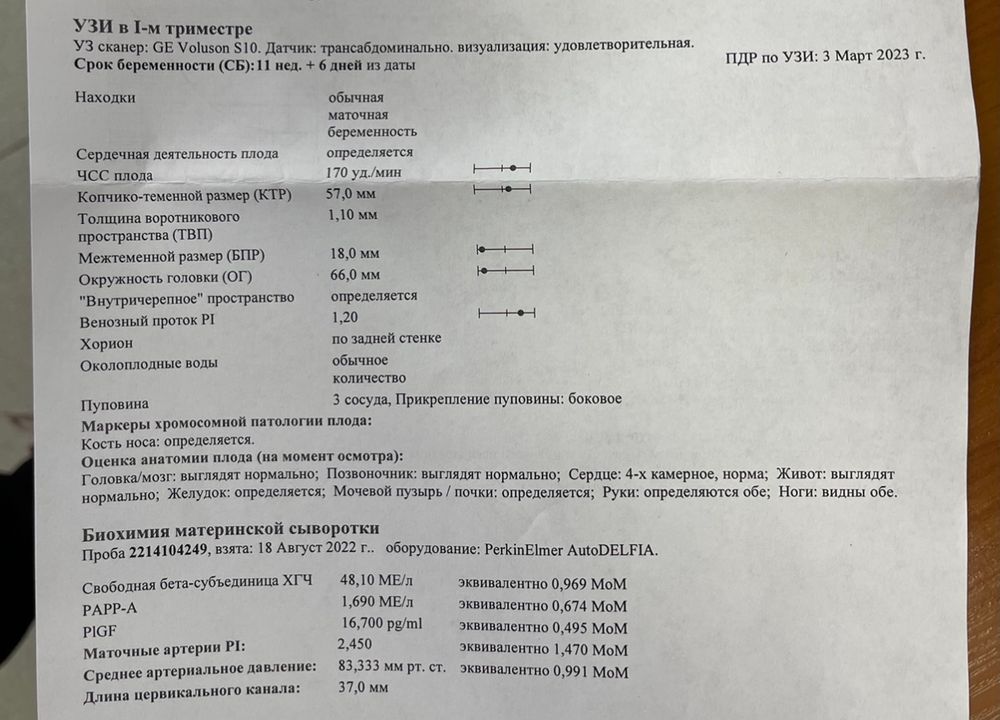

Формирование Плода в Первом Триместре: Важные Этапы